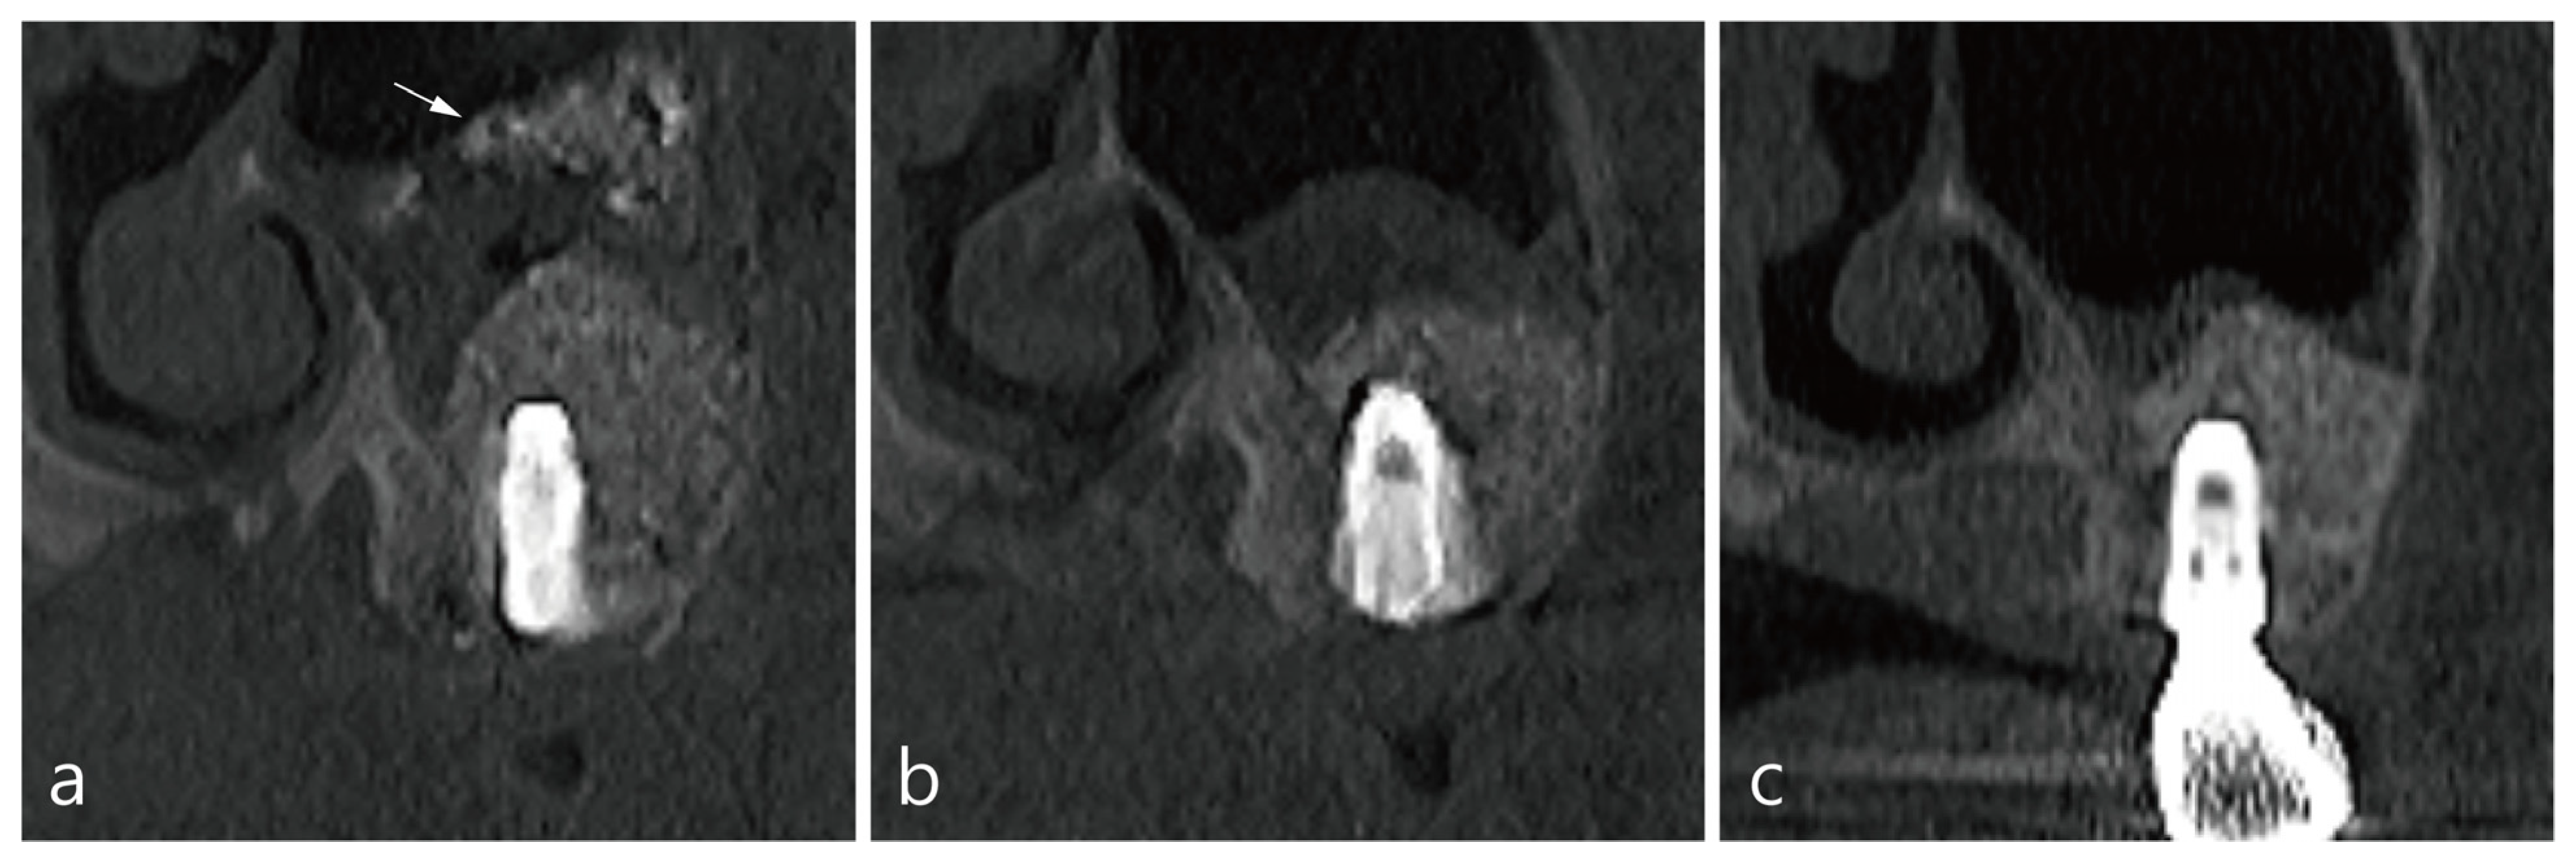

6. Case 4